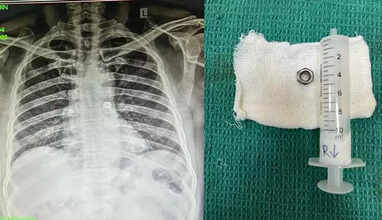

கோவை குனியமுத்துர் பகுதியை சேர்ந்தவர் சம்சுதீன்(55). இவர் எலக்ட்ரீசியனாக பணிபுரிந்து வருகிறார். இந்த நிலையில், நேற்று சம்சுதீன் பணியில் ஈடுபட்டிருந்தபோது, தவறுதலாக போல்ட் நட்டை விழுங்கி விட்டார். இதனால் அவருக்கு மூச்சுத்திணறல் ஏற்படவே, சக தொழிலாளர்கள் அவரை மீட்டு சிகிச்சைக்காக கோவை அரசு மருத்துவக் கல்லூரி மருத்துவமனைக்கு கொண்டு சென்றனர். அங்கு அவருக்கு மேற்கொள்ளப்பட்ட சிடி ஸ்கேன் எடுத்து பார்த்தபோது விழுங்கிய போல்ட் நட், அவரது இடது நுரையீரல் வழியாக செல்லும் மூச்சு குழாயில் சிக்கியது தெரியவந்தது. இதனை தொடர்ந்து, மருத்துவர்கள் குழு சம்சுதீனுக்கு மூச்சுக்குழாய் உள்நோக்கி கருவி மூலம் 15 நிமிட அறுவை சிகிச்சைக்கு பின்னர் வெற்றிகரமாக போல்ட் நட்டை வெளியே எடுத்தனர். அறுவை சிகிச்சைக்கு பின்னர் அவர் நன்றாக உள்ளார்.

இந்த சிறப்பு அறுவை சிகிச்சையை காது மூக்கு தொண்டை பிரிவு பேராசிரியர் மருத்துவர் அலி சுல்தான் தலைமையில், மருத்துவர்கள் சரவணன், மயக்கவியல் மருத்துவர்கள் மணிமொழி செல்வன், மதனகோபாலன் மற்றும் மருத்துவக்குவினர் இணைந்து வெற்றிகரமாக செய்து முடித்தனர். சவால் மிகுந்த இந்த அறுவை சிகிச்சையை வெற்றிகரமாக செய்து முடித்த மருத்துவ குழுவினருக்கு, கோவை அரசு மருத்துவக் கல்லூரி மருத்துவமனை முதல்வர் நிர்மலா பாராட்டு தெரிவித்தார்.